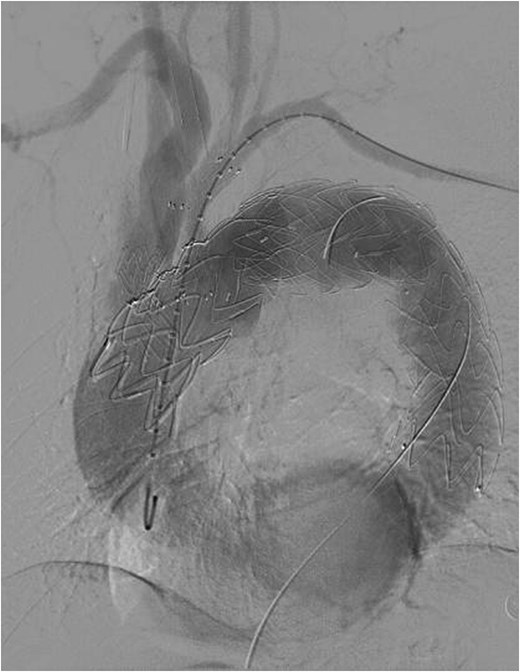

The patient underwent F/B TEVAR on August 17, 2022. Physician-modified stent-graft (PMSG) were deployed in all three branches of the arch. Aortic stent graft from Captivia, Medtronic, USA were utilized; Branch stent graft included iliac artery stent graft and coated stent graft, from Medtronic, BD, etc. Following stent graft placement, angiography revealed unobstructed flow in the three branches of the superior arch, and the arterial aneurysm disappeared completely (see Fig. 2). Due to the twisted aorta, the length of the aortic stent graft delivery system was insufficient, leading to the use of a common iliac artery-artificial vessel approach. The procedure was complicated by anastomosis rupture and massive hemorrhage, requiring a 1000 ml blood transfusion. Post-surgery, the patient was admitted to the intensive care unit and developed a high fever, significant hemoglobin drop, and unstable circulation. An urgent computed tomography revealed a retroperitoneal hematoma, which was removed on August 19, 2022. Intraoperative exploration uncovered a large number of blood clots, totaling ⁓1000 ml, with no obvious bleeding points found. The patient developed bacteremia, pulmonary infection, septic shock, acute kidney injury (KDIGO3 stage), and fungal infection. After long-term supportive treatment, the patient was transferred to a general ward on October 10, 2022, and discharged on October 28, 2022.